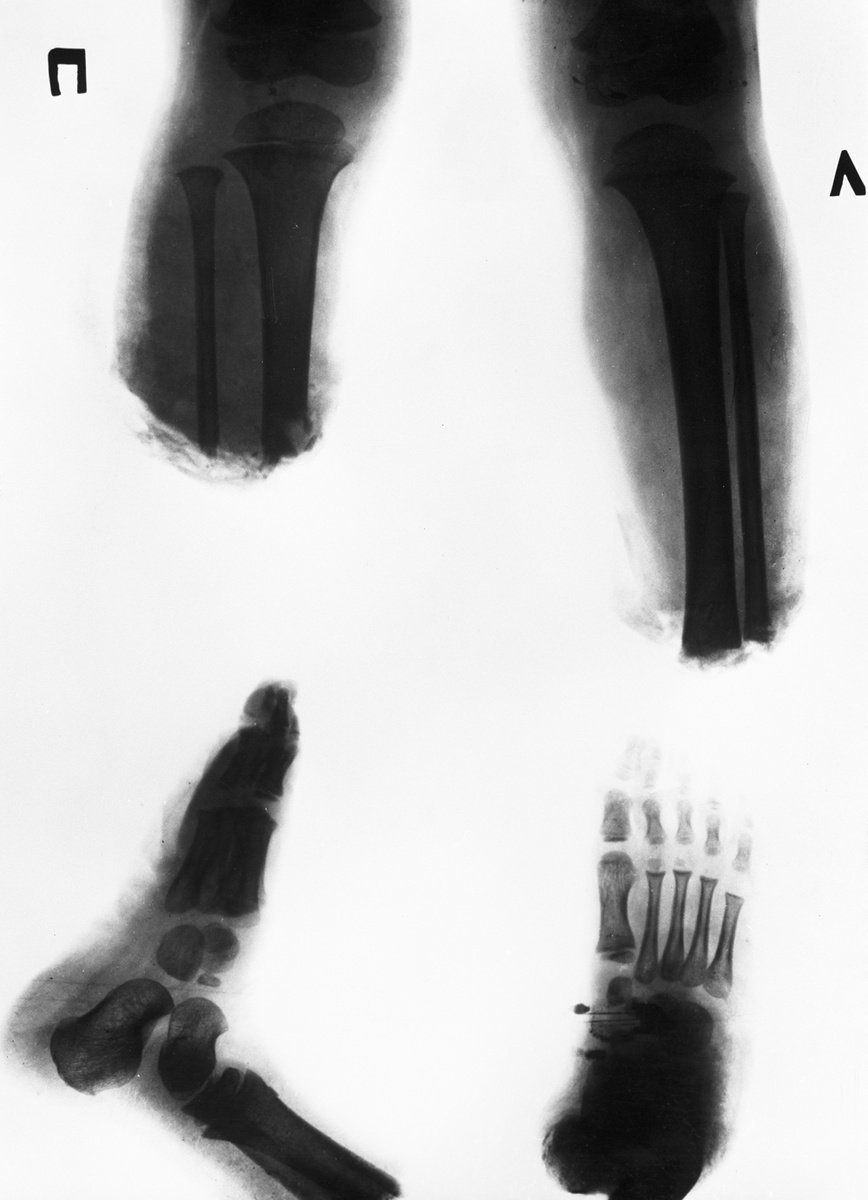

Представьте: лето, деревня в Литве, 1983 год. Трехлетняя девочка Раса играет во дворе, пока её бабушка косит траву ручной косилкой. Одно неловкое движение, крик — и тишина. Косилка перерезала обе ножки ребёнка чуть выше колен.

Ножки лежали в траве отдельно. Местные врачи, увидев ребёнка, только разводили руками: такого в СССР ещё не делали. Первую помощь оказали в литовской больнице, но спасти конечности могли только в Москве.

Девочку срочно отправили самолётом в столицу. Её приняла 51-я городская больница (сейчас — Филатовская). Главный хирург Рамаз Датиашвили, увидев ребёнка, принял решение, которое шло против всех инструкций: он решил попытаться пришить ноги. Это была авантюра, потому что успешных реплантаций (приживлений) целых конечностей в стране ещё не было.

Работа шла больше девяти часов. Под микроскопом хирурги сшивали артерии, вены, нервы, собирали по крупицам раздробленные кости. Успех зависел от каждого стежка.

После операции главный вопрос был: приживутся ли ноги? Первые дни показали — да, кровообращение восстановилось. Но это была только первая победа.